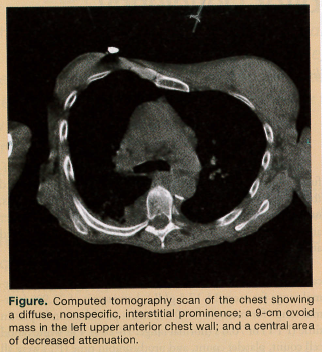

A computed tomography scan of the chest showed a diffuse, nonspecific, interstitial prominence, which reflected the chronic changes of COPD (Figure). A 9-cm ovoid mass, isodense with the musculature, was found in the left upper anterior chest wall. A questionable central area of decreased attenuation was seen, potentially indicating fluid collection.